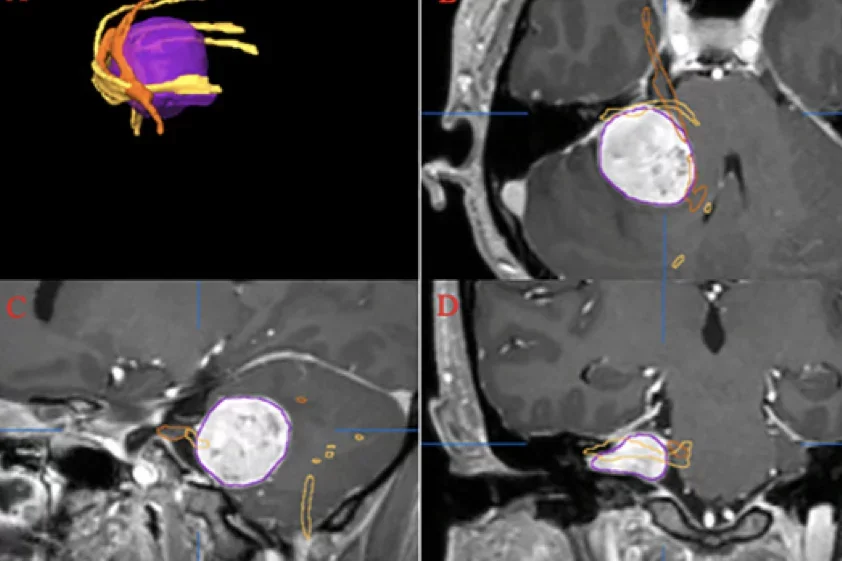

Ung, N. et al. Accuracy and outcomes of diffusion sensor imaging tractography in resection for vestibular schwannomma for facial nerve preservation. Journal of the neurological sciences. 430 (2021) 120006

MVI Measured on axial T2-weighted MR images using the ITK-SNAP software.